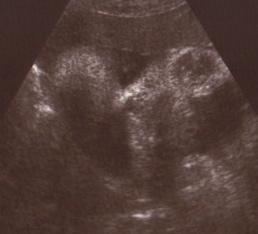

Tilt your head all the way to the left and squint. Soften your gaze & use your baby ultrasound imagination (hint: this is a close-up of her face). If you’re lucky, you’ll be able to make out 2 eyes, a nose and a mouth with 2 little fists on each side of her chin. That’s Zoe!

But back to the checkup… First of all, there’s a real baby in there! AND she’s still a girl (thank goodness), and according to the doc, she has Bart’s nose, which he found reassuring. She’s also right on track for birth weight (between 4-5 pounds, though apparently 3rd trimester weight “guestimates” are notoriously wrong). In fact, we learned something: baby weight is gauged through ultrasound by measuring head, abdomen and femur length. They also check size by seeing where those measurements lie in number of weeks of development…

Zoe’s head = 32 weeks (right on track)

Zoe’s abdomen = 31.5 weeks (also AOK)

Zoe’s femur length = 35 weeks (WOWZA!)

Yes, that femur length is very unusual (google “long femur fetus” and you’ll see what I mean). Of course, I googled it immediately, but then, I’m a big nerd. According to the doctor, that just means she might be tall – and very likely at least she’ll be a long baby at birth. Good news is that femur length does NOT make birth any more difficult – whew! If her HEAD had measured 35 weeks, I’d be in tears… The BBC even seems to think that long femur length equals lower blood pressure as an adult!